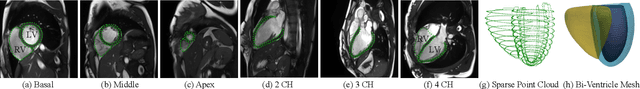

Abstract:We propose a novel neural deformable model (NDM) targeting at the reconstruction and modeling of 3D bi-ventricular shape of the heart from 2D sparse cardiac magnetic resonance (CMR) imaging data. We model the bi-ventricular shape using blended deformable superquadrics, which are parameterized by a set of geometric parameter functions and are capable of deforming globally and locally. While global geometric parameter functions and deformations capture gross shape features from visual data, local deformations, parameterized as neural diffeomorphic point flows, can be learned to recover the detailed heart shape.Different from iterative optimization methods used in conventional deformable model formulations, NDMs can be trained to learn such geometric parameter functions, global and local deformations from a shape distribution manifold. Our NDM can learn to densify a sparse cardiac point cloud with arbitrary scales and generate high-quality triangular meshes automatically. It also enables the implicit learning of dense correspondences among different heart shape instances for accurate cardiac shape registration. Furthermore, the parameters of NDM are intuitive, and can be used by a physician without sophisticated post-processing. Experimental results on a large CMR dataset demonstrate the improved performance of NDM over conventional methods.